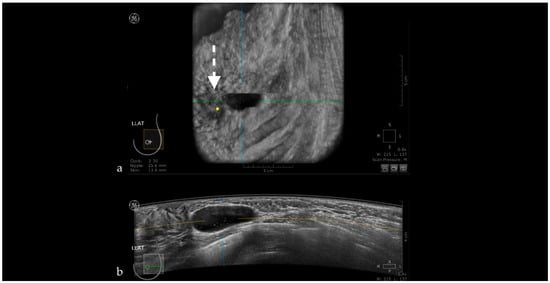

Nipple Artifact

The retro areolar region is difficult to assess due to the shadowing artifact induced by the nipple that appears as hypoechoic columns extending in the anterior-posterior direction behind the nipple. This artifact can be caused by an imperfect adjustment of irregular nipple surface, and if an abnormality is suspected, the patient is recalled for rescanning or for an HHUS (Figure 6) [44].

Figure 6. Hypoechoic columns (white arrow—b) behind the nipple (yellow dot—a) interfering with the evaluation of the breast tissue: nipple artifact.